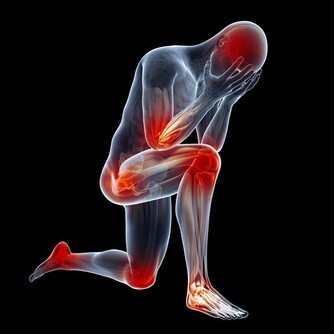

大部分人身體都有濕氣,濕氣剛剛侵入你的身體時你會常感到四肢無力,頭昏沉,總睡不夠,

這些你不去注意,時間就了濕氣就會引發出一些大毛病比如:

如:高血壓、哮喘、脂肪肝、心腦血管等疾。

Ⅱ)多運動

運動可以排毒,體內濕氣重的人大多數都是飲食油膩、缺乏運動的人。

這些人常常會感覺身體沉重、四肢無力而不願活動,但越是不愛運動,體內淤積的濕氣就越多,

久而久之,必然就會導致濕氣攻入脾臟,引發一系列的病症。

運動可以緩解壓力,促進身體器官運作,加速濕氣排出體外。

跑步、健走、游泳、瑜珈、太極等運動,有助活化氣血循環,增加水分代謝。